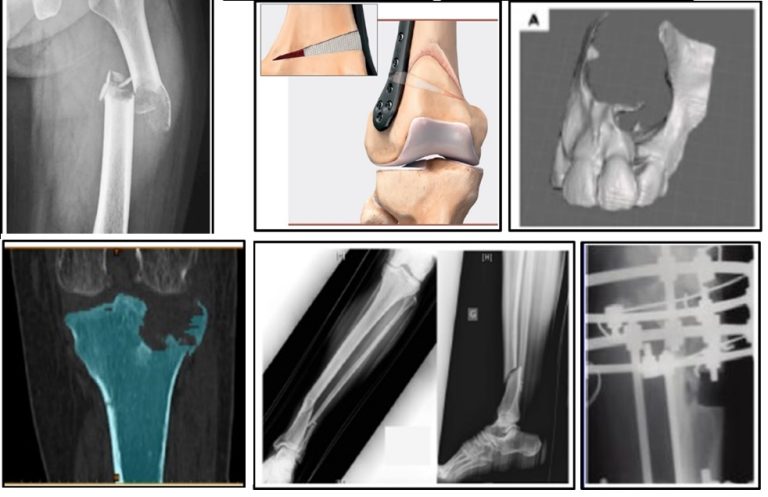

کاربرد گرافت استخوانی در ساختار داربست برای جایگزینی موقت در محل بافت استخوانی ازبین رفته و تحریک تشکیل بافت استخوانی جدید در محل آسیب دیده می باشد. در زیر تنوع آسیب های استخوانی ارایه می گردند:

• ترمیم استخوان متافیزیز (Bone Metaphysis Substitution)

• ترمیم استخوان تمور یا کیست خوش خیم استخوانی (Bone Benign Tumor or Cyst Substitution)

• ترمیم استخوان دهان، فک و صورت (Bone Oral and Maxillofacial Substitution)

• ترمیم استخوان بین مهره ای (Bone Intervertebral Substitution)

• ترمیم استخوان بازسازی انحراف استخوانی (Bone Deformity Reconstruction Substitution)

• ترمیم استخوان در شکستگی های شدید (Bone Reconstruction in Severe Fracture Pattern in Mid-Shaft Section)

• ترمیم شکستگی استخوان در محل خط شکست در شکستگی های استخوانی (Bone Healing at the Fracture Gaps)

• ترمیم بافت استخوانی فک برای کاشت ایمپلنت دندان (Bone Reconstruction at the Jaw and Maxilla for Dental Implant Insertion)

مثال هایی از استفاده گرافت استخوانی در ساختار داربست